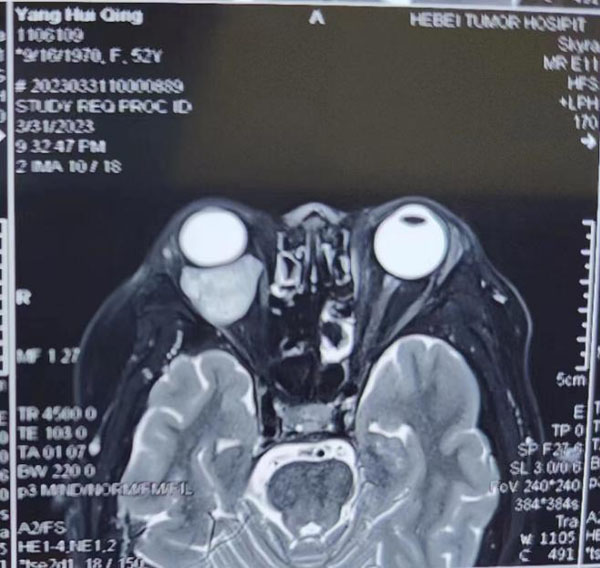

患者主因右眼视物不清伴眼球突出3年,以右眼眶内占位收入我院眼科。眼科郝玉华教授在检查中发现,患者右眼视力极低,右眼上睑下垂,眼球突出且运动明显受限。眼眶CT提示眶内巨大占位,几乎占据球后整个眶间隙。同侧额部颅骨骨质亦显示巨大肿瘤,约7*7 cm大小。患者已经有上睑下垂和视力明显下降的症状,表明肿物已经对眶上裂神经和视神经有一定压迫。